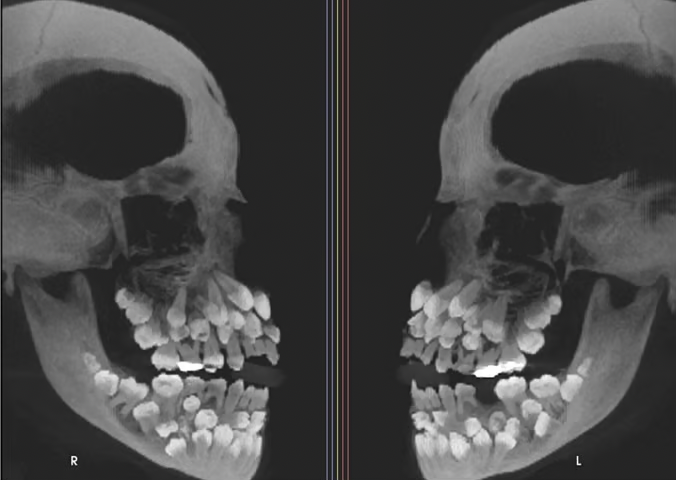

11세 소녀 입 안에서 치아가 무려 81개나 발견돼 학계에 충격을 주고 있다. 지난 15일 VN익스프레스 등 외신은 브라질에 사는 11세 소녀가 위쪽 유치 1개를 뽑기 위해 병원을 찾았는데 엑스레이 촬영 결과 소녀의 입안에서 유치 18개와 영구치 32개, 과잉치 31개 등 총 81개 치아가 발견됐다고 보도했다.

일반적으로 성인 기준 32개인 정상 치아 수를 넘는 추가 치아가 발견되는 것을 '다발성 과잉치증(multiple hyperdontia)'으로 부른다.

이번 사례처럼 30개가 넘는 과잉치가 확인된 사례는 전 세계적으로도 매우 드물다. 해당 사례는 브라질 미나스제라이스주 주이스지포라 연방대학교 치과병원 연구팀이 진료 중 확인한 것으로 미국 치과교정·악안면외과학회지에 보고됐다.